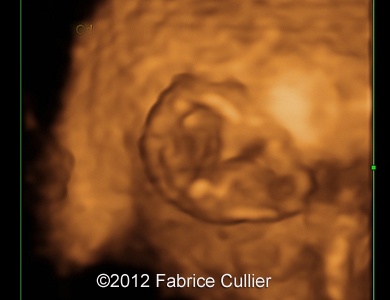

Image 7: 3D evaluation of the face was done.

3A